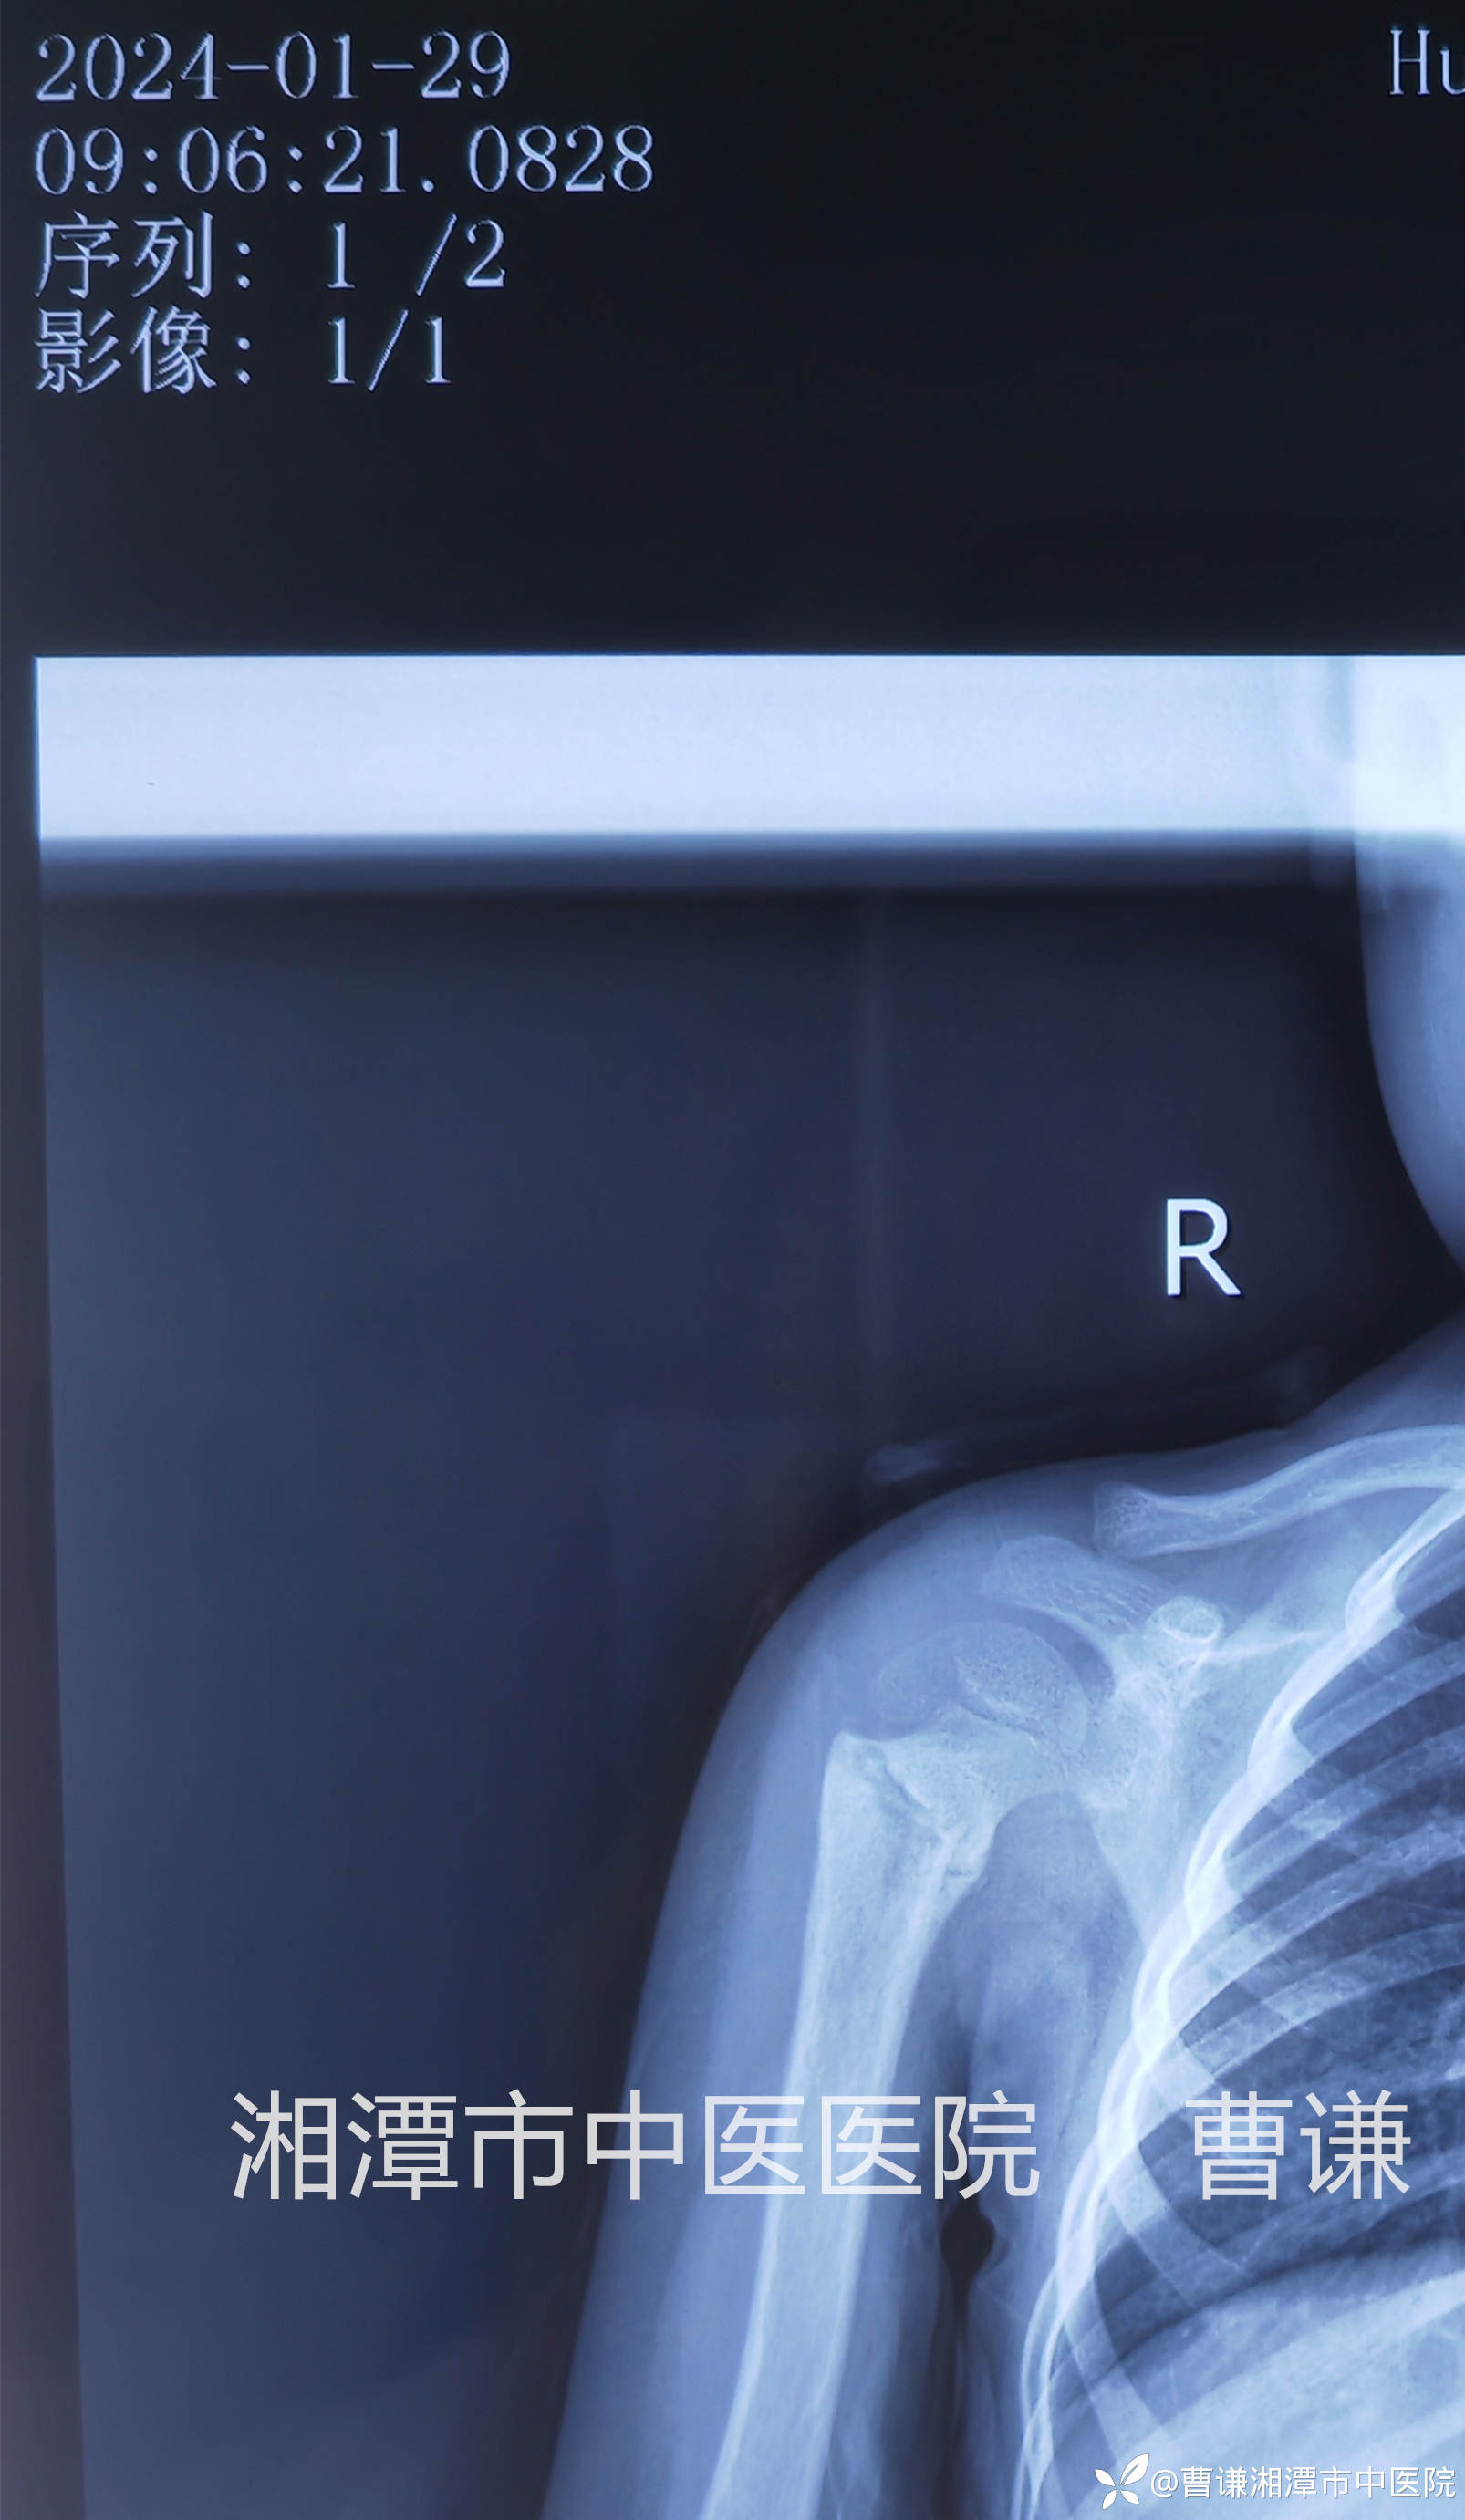

伤后9天拍片复查位置同前,既然小患者不吵不闹,天天开心的在病房走廊里瞎逛,管床大夫悬着的心也放下来了。我每天会隔着夹板压一压骨折端,问一问痛不痛,回答我的总是那个稚嫩的声音:“不痛”。然后我会带着夹板给孩子被动进行肩关节前屈、外展活动。

伤后23天拍片复查见骨折端有明显骨痂生长,予以拆除外固定,指导患者进行主动功能锻炼。

伤后23天患者肩关节上举、内旋、外旋、肘关节屈伸及前臂旋转功能均基本恢复正常。